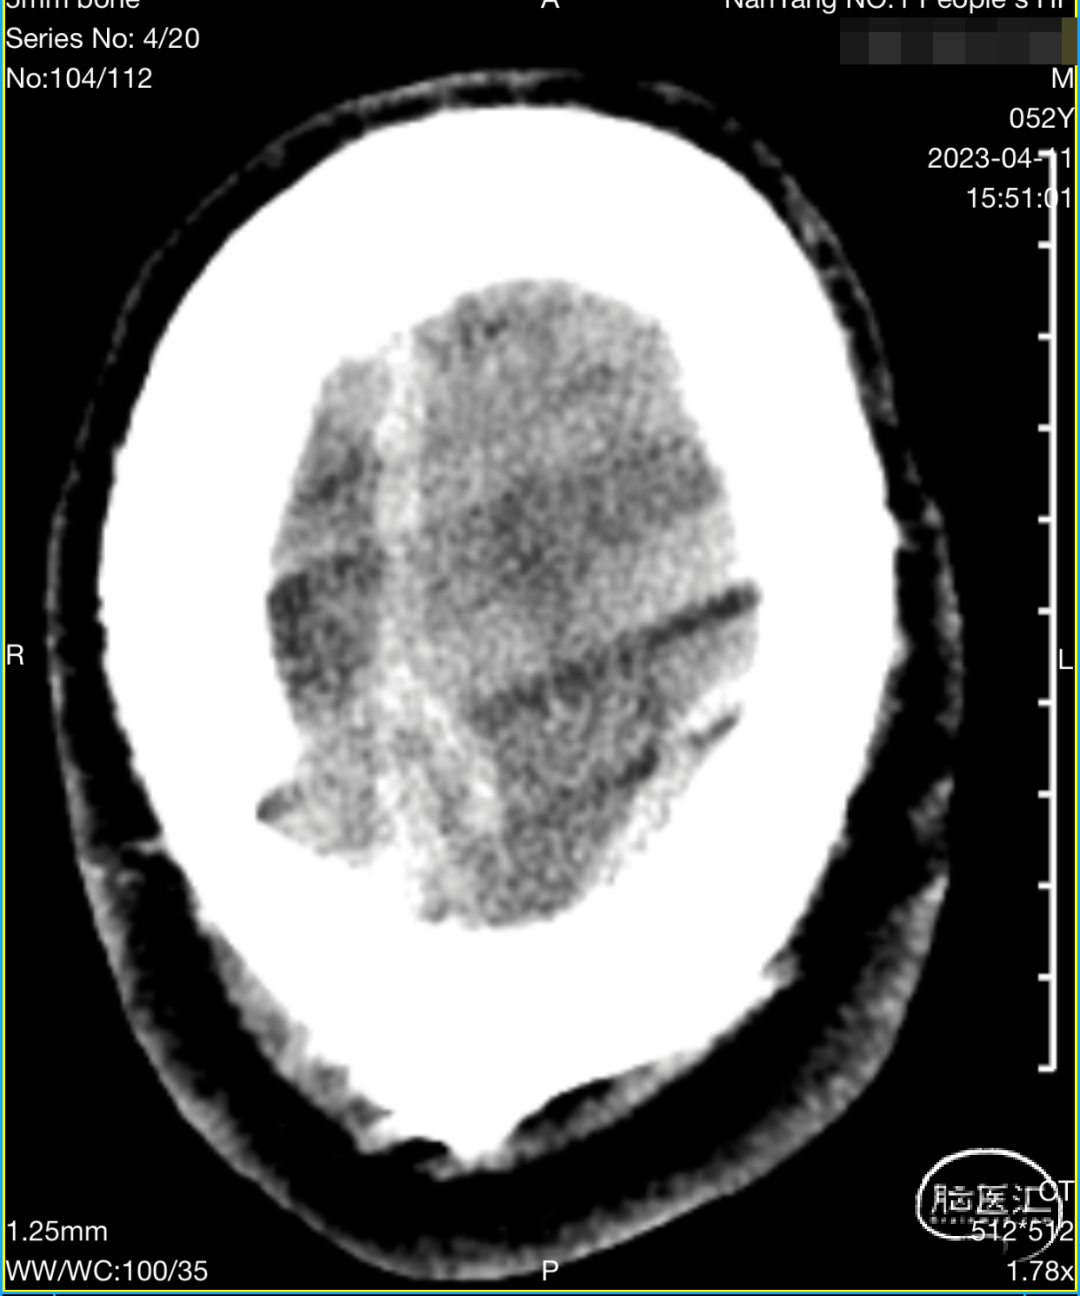

入院影像检查

CT显示左侧顶叶低密度水肿影,内见高密度血肿影;上矢状窦高密度,考虑上矢状窦血栓可能大。